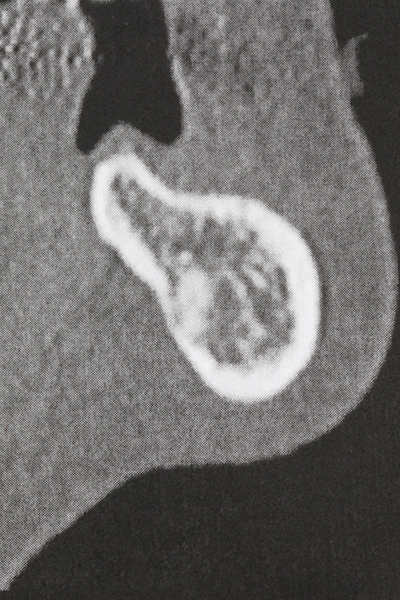

Indikation: Sinuslift

Die Präparation des lateralen Fensters bei der externen Sinusbodenelevation stellt gerade für chirurgisch unerfahrene Implantologen eine große Herausforderung dar. Die knöcherne Bedeckung der Kieferhöhle ohne eine Verletzung der darunterliegenden Schneider’schen Membran abzutragen ist dabei nur ein Teil der Operation – nach Schaffung eines ausreichenden Zugangs muss die Kieferhöhlenschleimhaut vorsichtig mobilisiert werden, um Raum für das einzubringende Material bzw. die Implantate zu schaffen. In dieser Indikation ist die Piezochirurgie zweierlei hilfreich: zum einen kann durch Verwendung diamantierter Instrumente eine selektive Knochenabtragung erfolgen und die darunter liegende Schleimhaut bleibt bei vorsichtiger Vorgehensweise intakt. Zum anderen unterstützen die Ultraschallfrequenzen zusätzlich eine komplikationslose Ablösung der Schleimhaut – sie werden durch spezielle stumpfe Ansätze in den Spaltraum zwischen Schleimhaut und Kieferhöhlenboden übertragen (Cassetta, Ricci et al. 2012, Pereira, Gealh et al. 2014) (Rickert, Vissink et al. 2013). So erscheint es nicht verwunderlich, dass in aktuellen Übersichtsarbeiten über die externe Sinusbodenelevation neben der Verwendung von rauen Implantatoberflächen und dem Einsatz von Knochenersatzmaterialien auch der Einsatz von piezoelektronischen Geräten als positiv bewertet wird (Wallace, Tarnow et al. 2012).